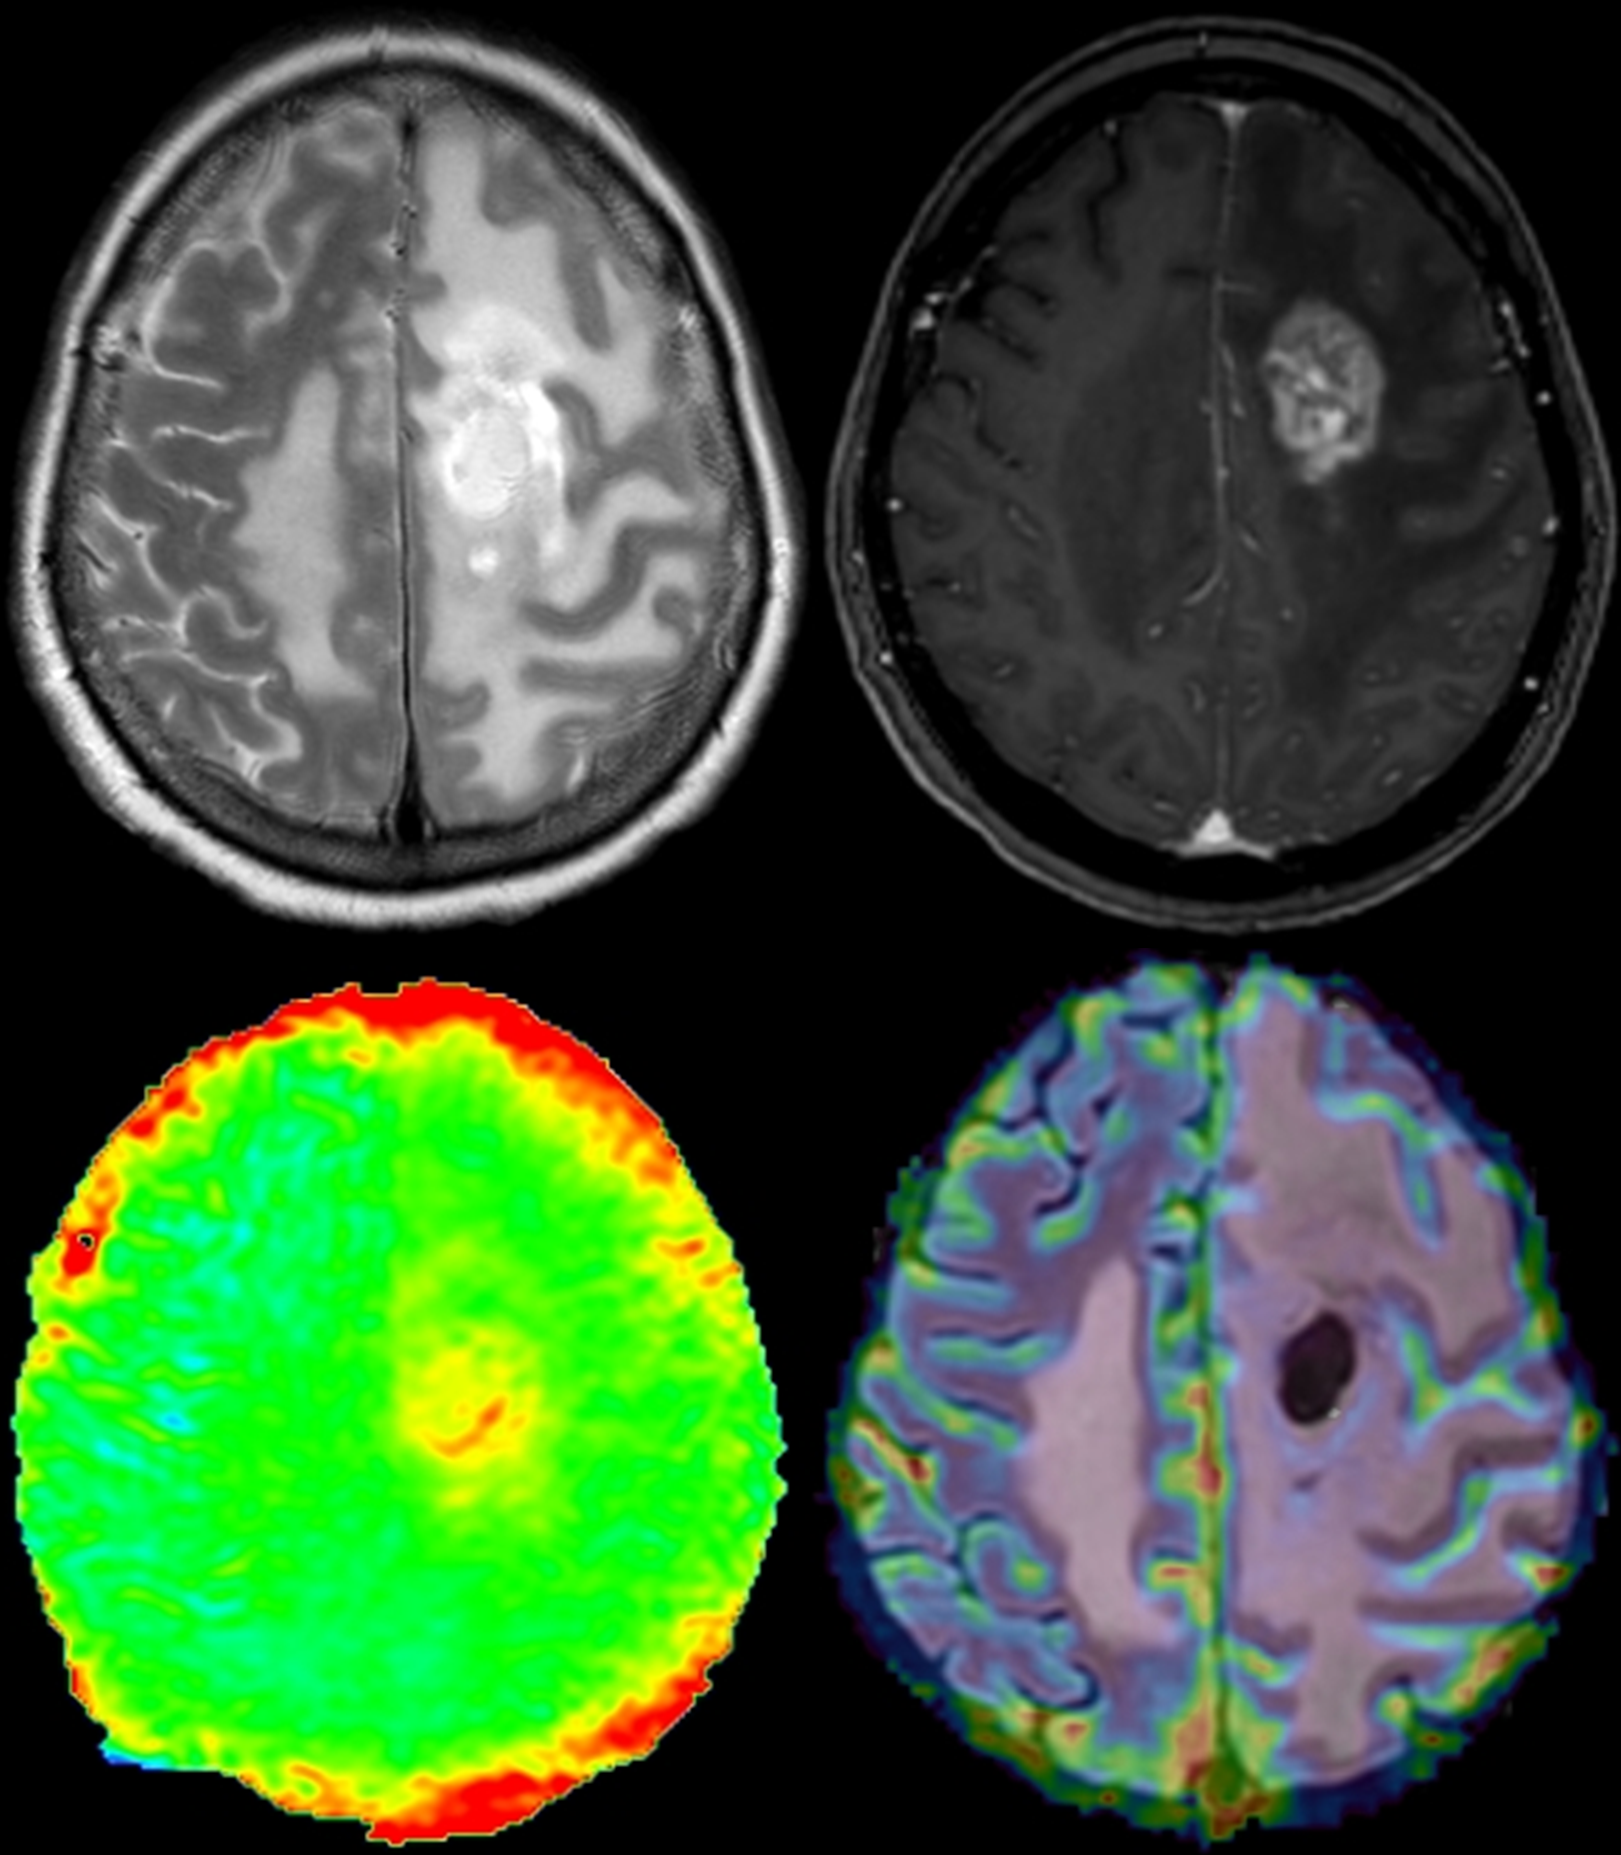

Magnetresonanztomographie (MRT)

MRT des Schädels, Spinalkanals und peripherer Nerven einschließlich funktioneller, mikrostruktureller und metabolischer Verfahren (Perfusions- und Diffusions-Tensorbildgebung, fMRT, MR-Spektroskopie, amide proton transfer - Imaging) sowie MR-Angiographie.

Es stehen vier moderne Magnetresonanztomographen (3,0 und 1,5 Tesla) zur Verfügung, die gemeinsam mit der Klinik für Radiologie genutzt werden.